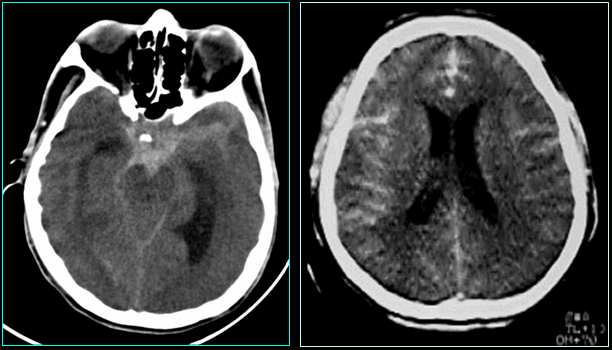

Ảnh chụp phát hiện xuất huyết dưới nhện của thai phụ. Ảnh: BSCC

Trường hợp thai phụ N., sau khi hội chẩn và cân nhắc các nguy cơ, bác sĩ quyết định mổ lấy thai ở tuần thứ 37 và tiếp tục can thiệp mạch máu não điều trị cho chị N. sau sinh để giữ an toàn cho cả mẹ và thai nhi. Ê- kíp đã can thiệp kịp thời và đã giúp chi N có ca sinh mổ an toàn.

Sau đó, sản phụ được tiếp tục chỉ định chụp DSA để xác định túi phình động mạch não và được can thiệp bít túi phình mạch não tại chỗ. Hiện tại, con của chị N đã được đưa về nhà chăm sóc, riêng chị vẫn được chăm sóc và theo dõi.